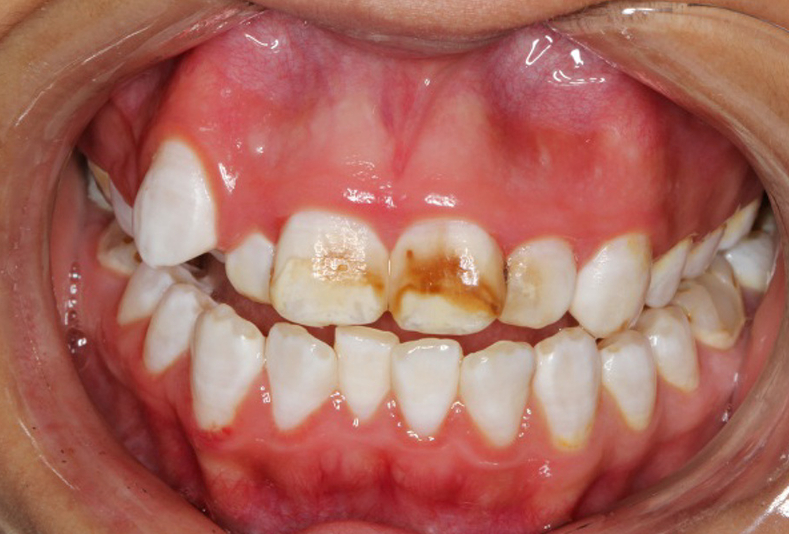

Casi clinici sull'applicazione della tecnologia QFL per il trattamento delle lesioni dello smalto

Igiene dentale

lesioni dello smalto

Applicazione della Fluorescenza quantitativa indotta per il trattamento delle lesioni dello smalto